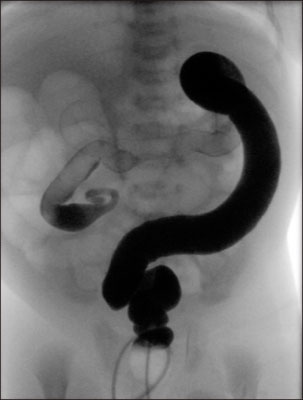

Total colonic aganglionosis in a 3-day-old boy. Question-mark shape of the colon is noted with cecum and ascending colon. The rectum and descending colon has normal caliber (case 15).

Fig. 2 Total colonic aganglionosis in a 3-day-old boy. Question-mark shape of the colon is noted with cecum and ascending colon. The rectum and descending colon has normal caliber (case 15).